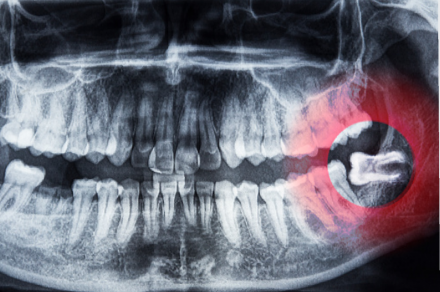

親知らずの知識

親知らずは全て抜いたほうが良いのか?